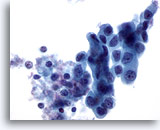

Figure 68

Lymph node FNA, atypical lymphoid proliferation.

The specimen is cellular and when compared to small lymphocyte a the majority of cells are slightly larger than this cell. The monotony of the sample is worrisome. 20x

Lymph node FNA, atypical lymphoid proliferation.

The specimen is cellular and when compared to a small lymphocyte the majority of cells are slightly larger than this cell. The monotony of the sample is worrisome.

20x

Figure 69

Lymph node FNA, atypical lymphoid proliferation.

Once again when a small lymphocyte is picked out, the majority of cells are larger. There is no range of maturity in this specimen. 40x

Lymph node FNA, atypical lymphoid proliferation.

Once again when a small lymphocyte is picked out, the majority of cells are larger. There is no range of maturity in this specimen.

40x

Figure 70

Lymph node FNA, atypical lymphoid proliferation.

A beautiful preparation. The nuclei are all oval with no nicks or cuts. The nucleoli are small and not hyperchromatic. 60x

Lymph node FNA, atypical lymphoid proliferation.

A beautiful preparation. The nuclei are all oval with no nicks or cuts. The nucleoli are small and not hyperchromatic.

60x

Figure 71

Lymph node FNA, atypical lymphoid proliferation.

Monotony, e.g. similar sized lymphocytes and the lack of tingible body macrophages, are the features of this atypical lymphoid proliferation. 60x

Lymph node FNA, atypical lymphoid proliferation.

Monotony, e.g. similar sized lymphocytes and the lack of tingible body macrophages, are the features of this atypical lymphoid proliferation.

60x